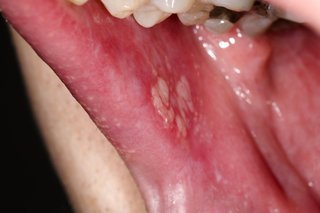

Białe plamy liszaja płaskiego w jamie ustnej.

Białe plamy w jamie ustnej mogą oznaczać liszaj płaski.